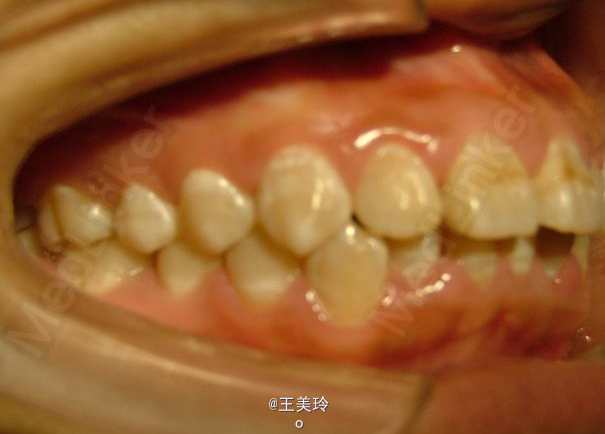

主诉:面突求矫治 既往史:无矫治史,无牙科治疗史,无外伤史,无过敏史,无口腔不良习惯,无家族遗传史 口腔检查:恒牙列,A7-B7;C7-D7。个别牙齿不齐 尖牙磨牙I类关系轻度深覆合深覆盖 下颌中线右偏约2mm 双颌前突,突面型 关节无弹响无压痛

诊断:安氏I类双颌前突 矫治计划 1.MBT矫治技术 2.拔牙矫治,拔A4B4C4D4 3.闭隙曲,J勾内收前牙 4.矫治结束后尖牙,磨牙,覆合覆盖正常 5.面型有所改善